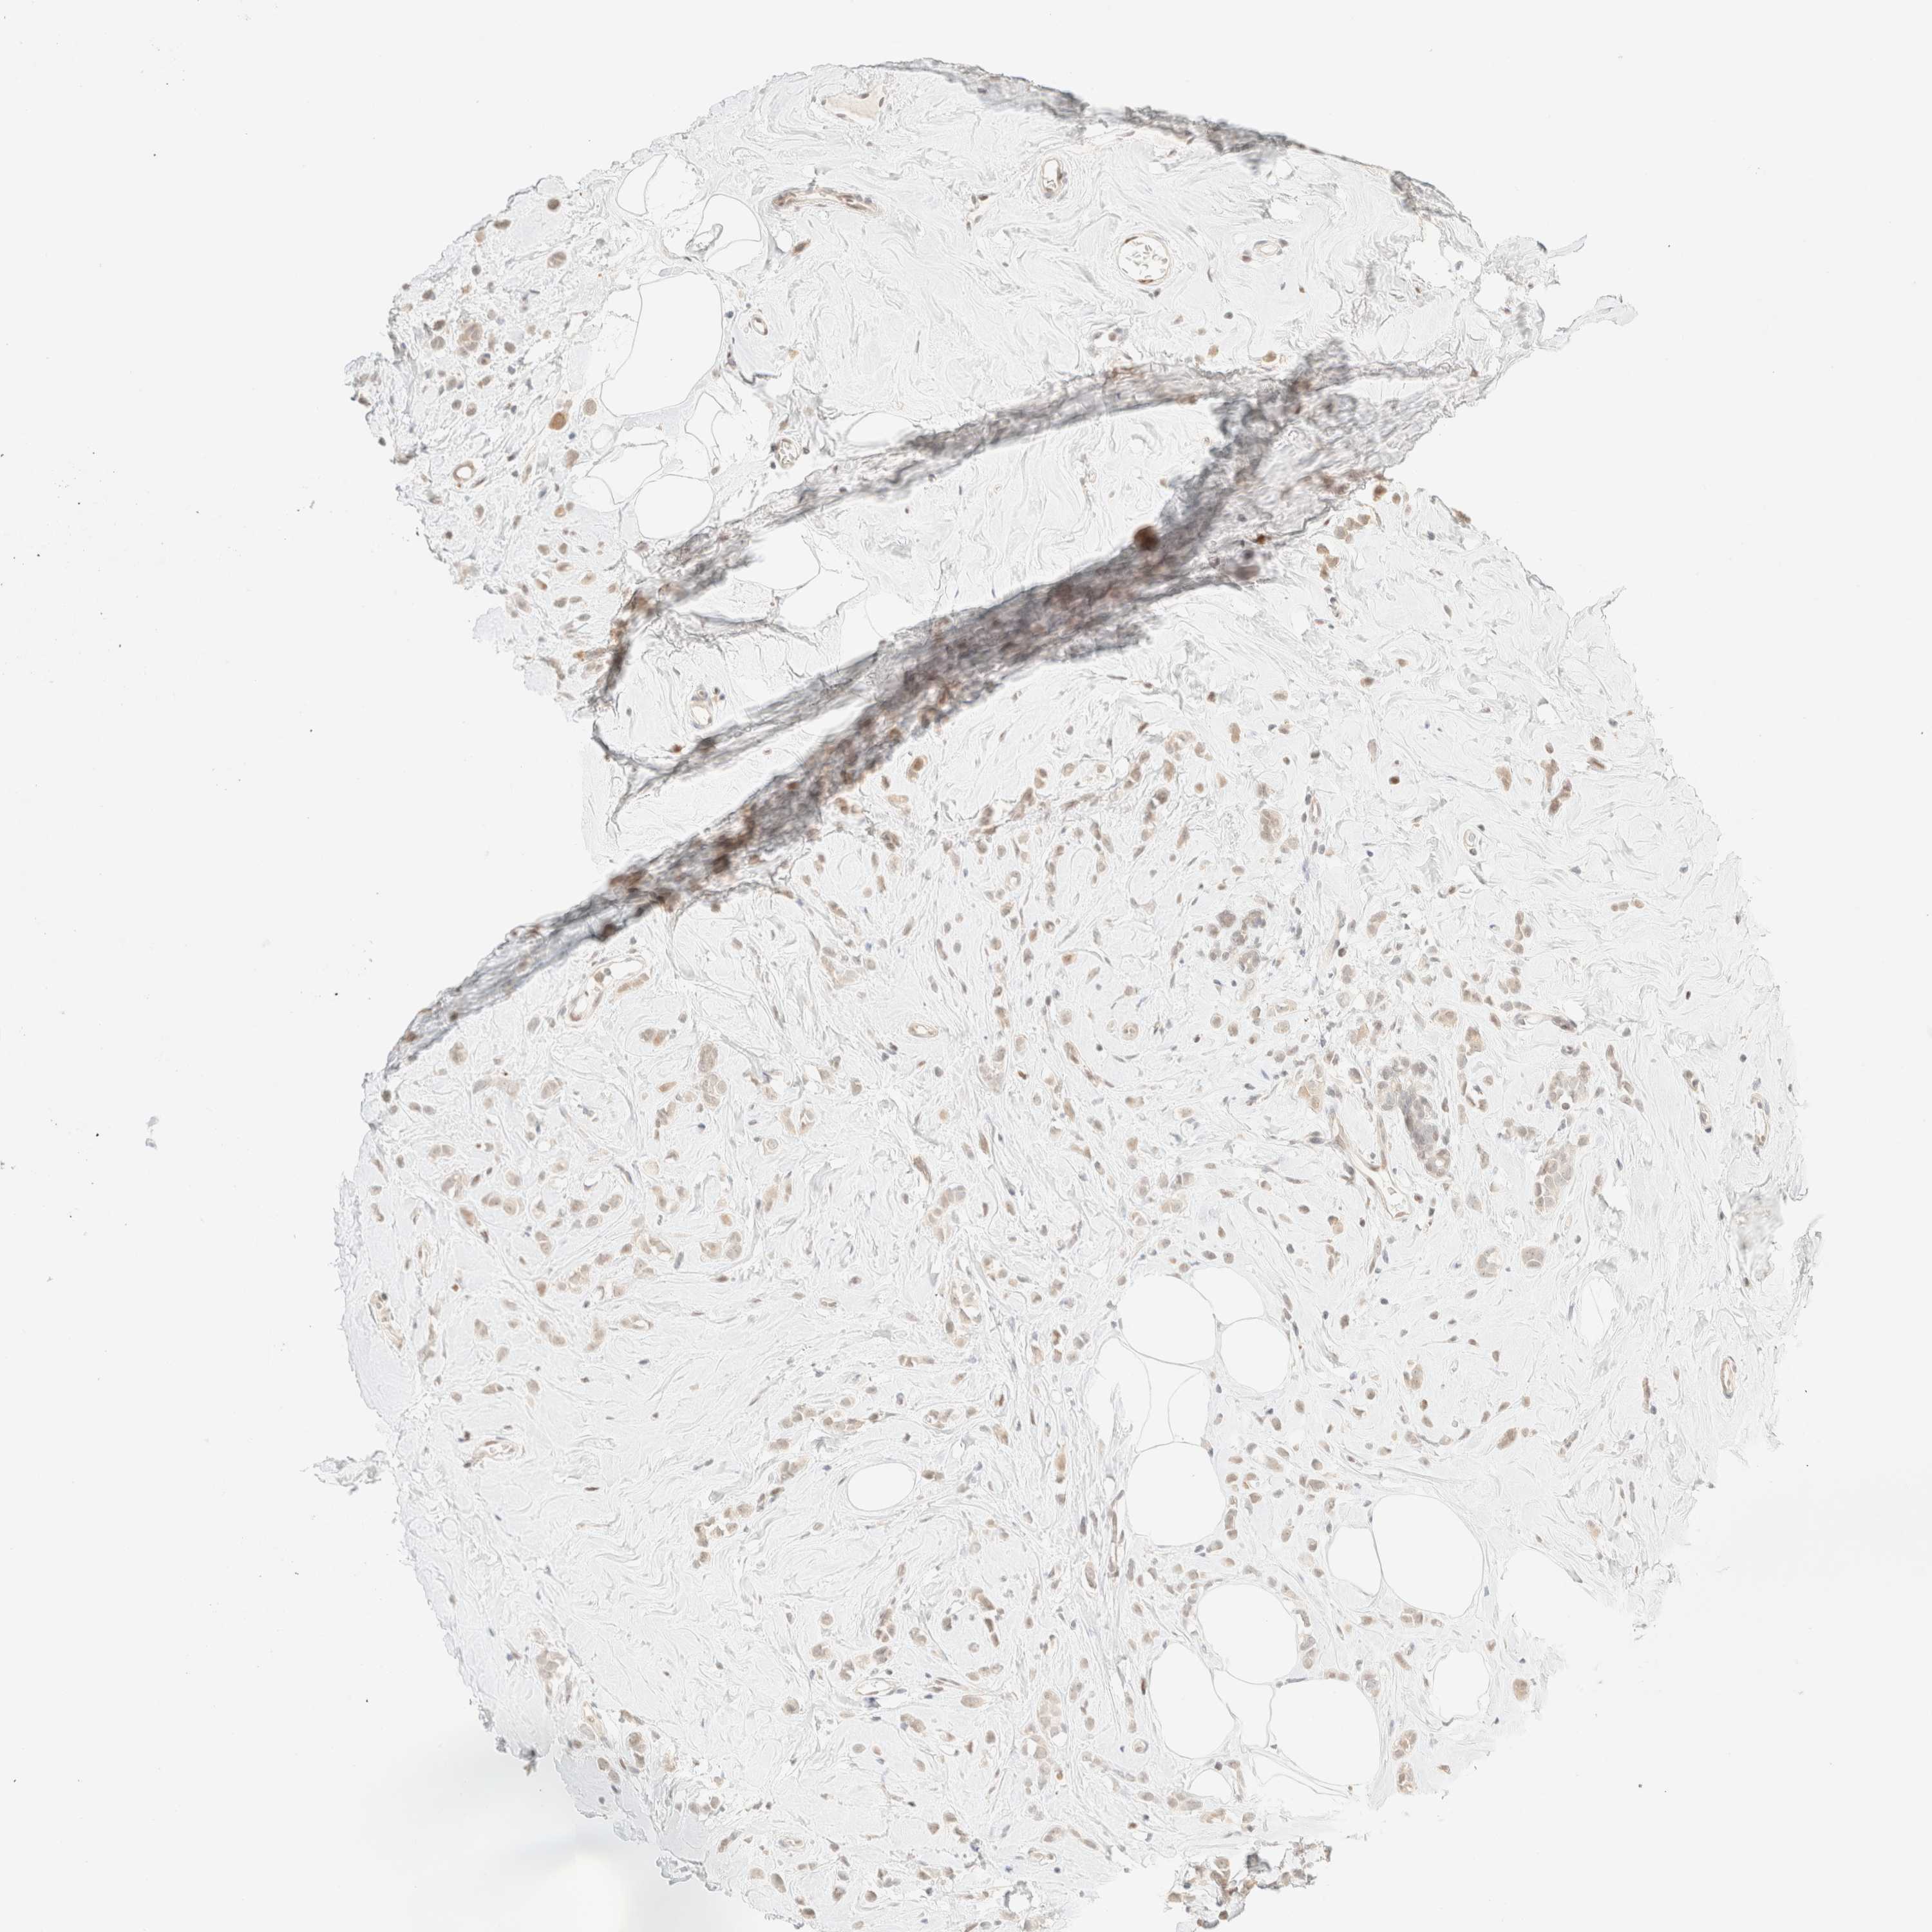

CANCER BREAST CANCER Show tissue menu

BRCA TCGA BRCA VALIDATION PROTEIN EXPRESSION

Breast cancer

Human cancer

Breast invasive carcinoma

TSR1 is not prognostic in Breast Invasive Carcinoma (TCGA)